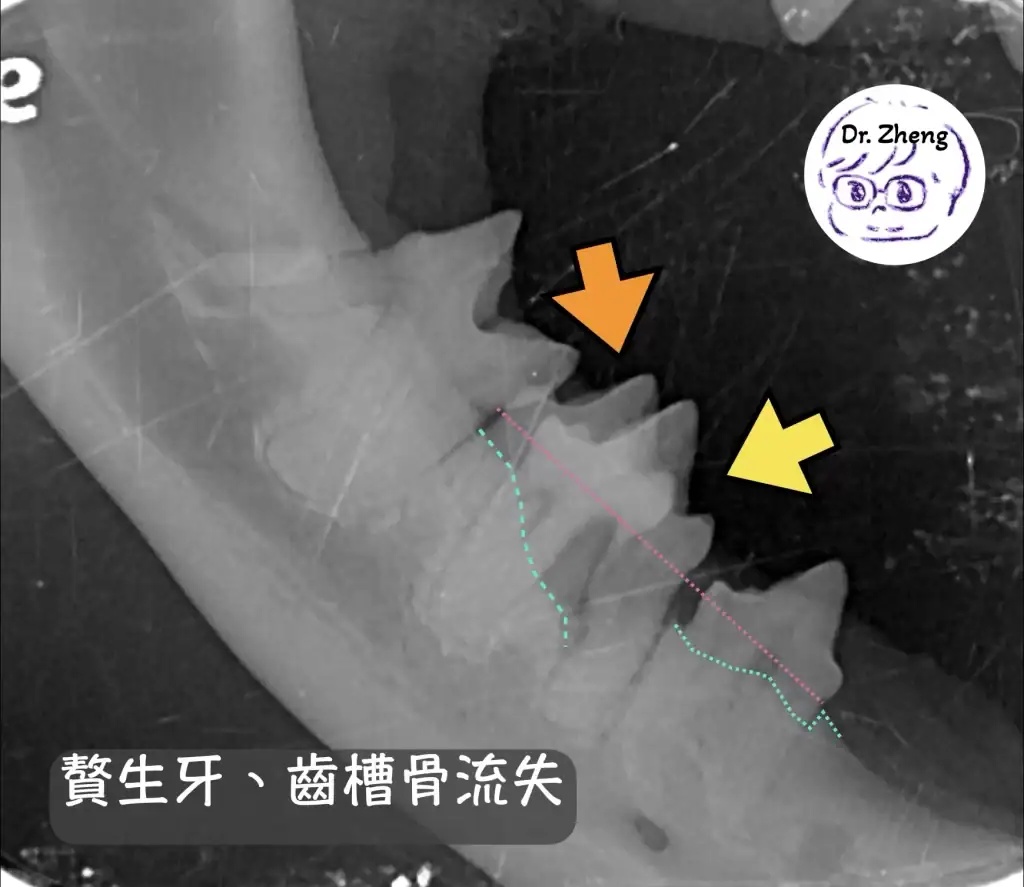

牙科X光檢查

口腔內出現多餘的牙齒,會使得有更多死角讓細菌得以藏匿,最終引發牙周病!

透過牙科X光我們得以評估牙根與鄰近結構的關係!